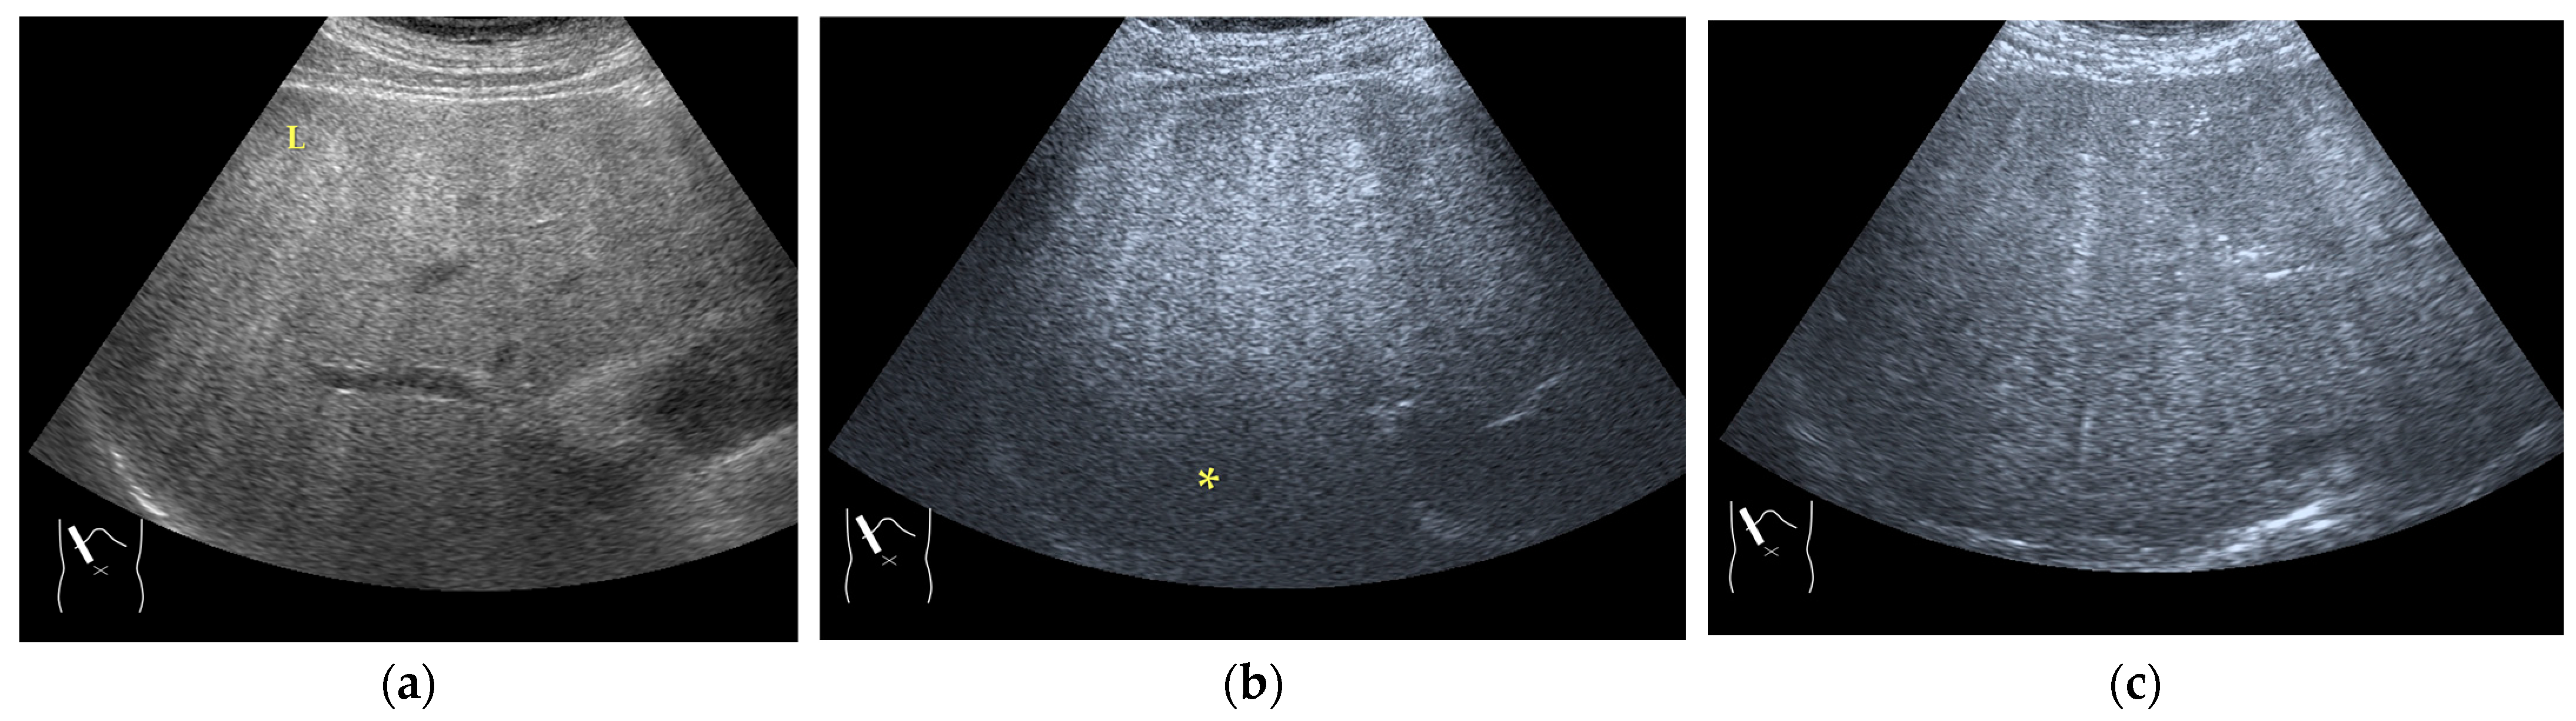

Figure 7.

Hypoenhanced area due to sound attenuation. (a) Gray-scale US of the liver (L) in a patient with alcoholic liver cirrhosis. (b) CEUS (4 MHz) shows that the deep area is hypoenhanced (*) compared with the upper area. (c) CEUS (3 MHz) shows the liver to be homogeneously enhanced.